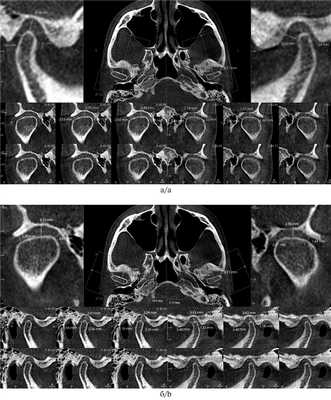

II. Оценка положения головок нижней челюсти в височно-нижнечелюстном суставе (ВНЧС). По КЛКТ можно приблизительно оценить положение головок нижней челюсти в суставных ямках: центральное соотношение, мезиальное или дистальное смещение. Данный метод, бесспорно, ценен для оценки структур ВНЧС, но для оценки внутрисуставной патологии рекомендуется использовать магнитно-резонансную компьютерную томографию [5, 6].

Японские ученые K. Ikeda, A. Kawamura и R. в 2011 г. [7] обследовали 22 человек и получили следующие средние размеры суставной щели: 1,3±0,2 мм — переднее суставное пространство, 2,5±0,5 мм — верхнее суставное пространство и 2,1±0,3 мм — заднее суставное пространство. В норме в трансверзальной плоскости медиальный полюс должен располагаться как можно ближе к стенке суставной ямки [8]. Если расстояние между медиальным полюсом и стенкой суставной ямки сильно различается между двумя суставами, это свидетельствует о смещении нижней челюсти в трансверзальном направлении. КЛКТ является отличным инструментом для анализа анатомической структуры суставных головок (рис. 5) [9].

Рис. 5. Ориентиры для измерения суставной щели [7].

а — размеры суставных щелей в кососагиттальном срезе; б — размеры суставных щелей в корональном срезе.